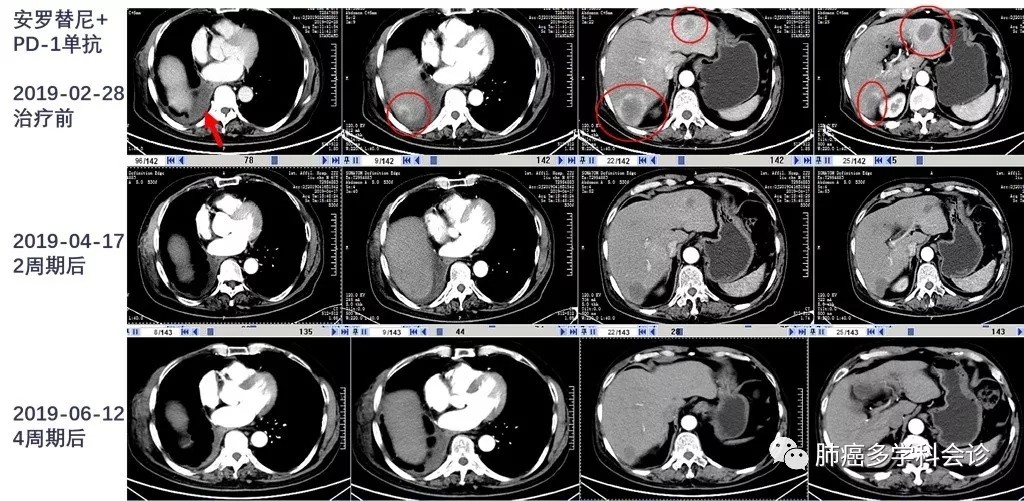

患者于2019-03-02 ~ 05-14在院外进行“安罗替尼+某种国产PD-1单抗”治疗4 周期。

在联合治疗的第 2和第 4周期,复查 CT 均显示肿瘤较前明显缩小:

6.webp.jpg